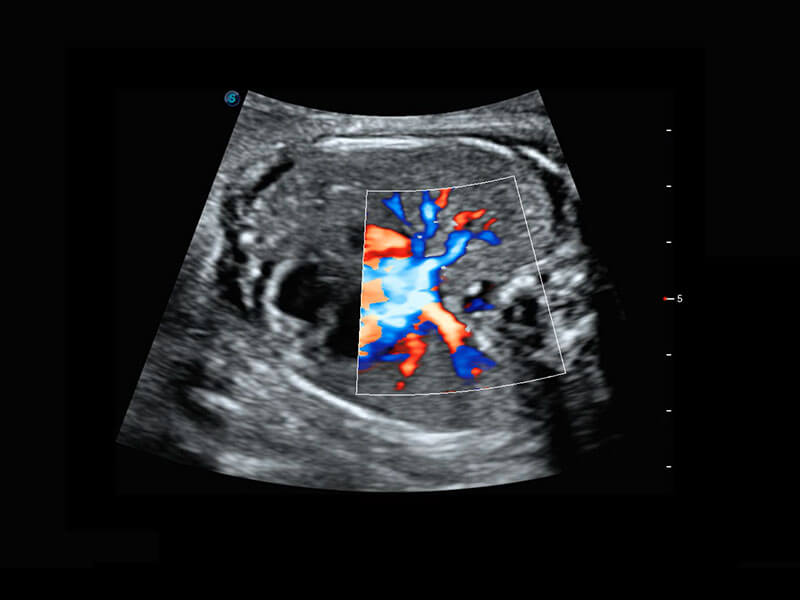

腔内妇科-宫腔分离

腔内妇科-卵巢